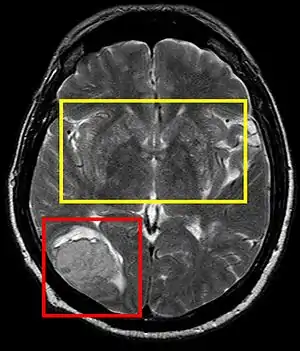

Cerebral softening, also known as encephalomalacia, is a localized softening of the substance of the brain, due to bleeding or inflammation. Three varieties, distinguished by their color and representing different stages of the disease progress, are known respectively as red, yellow, and white softening.[1][2]

Stroke brain (similar to cerebral softening)